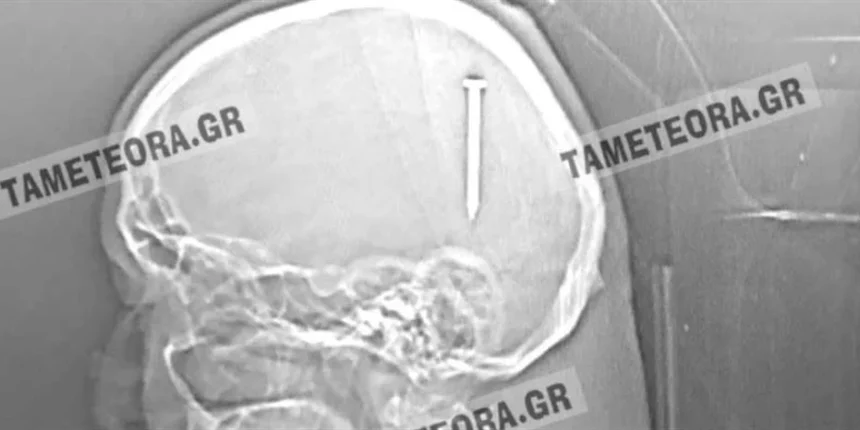

Όπως κατέγραψε η ιστοσελίδα tameteora.gr ο συμπολίτης μας βρέθηκε ξαφνικά με ένα καρφί 5 εκ. στο κεφάλι του κατά το διάστημα εργασιών που έκανε.

Εκτός από το αρχικό τράνταγμα που ένιωσε δεν ακολούθησε ούτε πόνος ούτε κάποιο άλλο σύμπτωμα.

Αρχικά μεταφέρθηκε στο Κέντρο Υγείας Καλαμπάκας, στη συνέχεια στο Γενικό Νοσοκομείο Τρικάλων και από εκεί στο Πανεπιστημιακό Νοσοκομείο Λάρισας, όπου του έγινε επέμβαση και του αφαιρέθηκε το καρφί με επιτυχία.

Πρόκειται πραγματικά για ένα σπανιότατο περιστατικό, ένα πραγματικό θαύμα, καθώς αν το καρφί βρισκόταν ελάχιστα χιλιοστά από το σημείο που σφηνώθηκε, θα ήταν πολύ επικίνδυνο για την υγεία του συμπολίτη μας με άγνωστα αποτελέσματα.